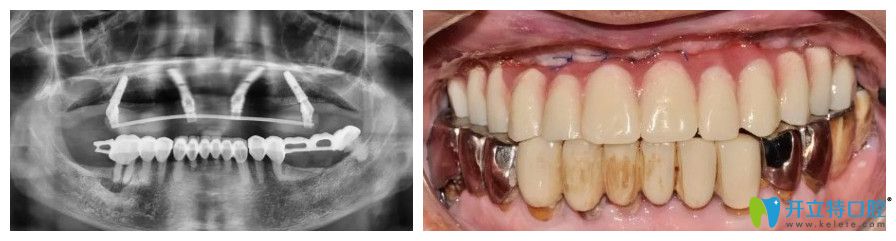

諾德齒科全口種植牙案例圖

張大爺,69歲

牙齒情況:上半口牙齒脫落

種植方式:微創(chuàng)即刻種植技術(shù)